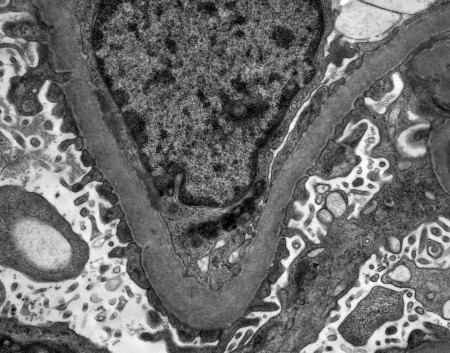

Ústav patologie a molekulární medicíny se zabývá komplexní laboratorní diagnostikou nádorových a nenádorových onemocnění. Využívá metod klasické histologie a cytologie s navazujícími dalšími speciálními laboratorními vyšetřovacími metodami. Ty zahrnují: pohled do buněk a tkání na úrovni ultrastrukturální analýzy (elektronová mikroskopie), průkaz exprese proteinů (metody imunohistochemické, Western blot, průtoková cytometrie), průkaz enzymové aktivity ve tkáňových řezech (enzymová histochemie), analýzu změn na úrovni chromozómů a genů a průkaz některých virů v histologickém řezu (metody in situ hybridizace) a rozbor DNA a RNA extrahovaných ze tkání (metody kvalitativní a kvantitativní polymerázové řetězové reakce, sekvenování). Vyšetřovaným biologickým materiálem jsou tkáně (nativní, zmrazené, fixované), punktáty kostní dřeně, periferní krev, případně jiné buněčné tekutiny (výpotky) a autologní štěpy pro transplantaci kostní dřeně.

Laboratoř neuropatologie a svalových biopsií (labNP) je součástí Ústavu patologie a molekulární medicíny UK 2. LF a FN Motol od roku 2002. Práce laboratoře je cílena na diagnostiku a výzkum onemocnění centrálního i periferního nervového systému a chorob kosterního svalu. Poskytuje kompletní bioptický diagnostický servis pro neurochirurgické a neurologické obory, a to nejen ve FNMH, dále spolupracuje s revmatologickými pracovišti a podílí se ve spolupráci s dalšími laboratořemi na diagnostice neuromuskulárních metabolických poruch.

Laboratoř neuropatologie a svalových biopsií (labNP) je součástí Ústavu patologie a molekulární medicíny UK 2. LF a FN Motol od roku 2002. Práce laboratoře je cílena na diagnostiku a výzkum onemocnění centrálního i periferního nervového systému a chorob kosterního svalu. Poskytuje kompletní bioptický diagnostický servis pro neurochirurgické a neurologické obory, a to nejen ve FNMH, dále spolupracuje s revmatologickými pracovišti a podílí se ve spolupráci s dalšími laboratořemi na diagnostice neuromuskulárních metabolických poruch.